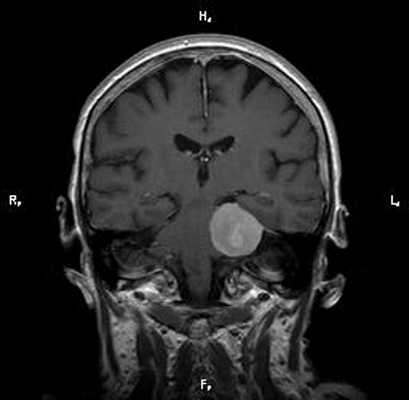

Диагноз: Онкология. Менингиома мосто-мозжечкового угла

При МРТ головного мозга в левом мосто-мозжечковом углу определялось больших размеров округлой формы внемозговое патологическое образование, с четкими ровными контурами, широким основанием, прилежащее к твердой мозговой оболочке. После внутривенного контрастирования отмечалось равномерное, выраженное усиление интенсивности МР-сигнала от вышеописанного образования, а также твердой мозговой оболочки. Пациенту был поставлен диагноз (менингиома левого мосто-мозжечкового угла).